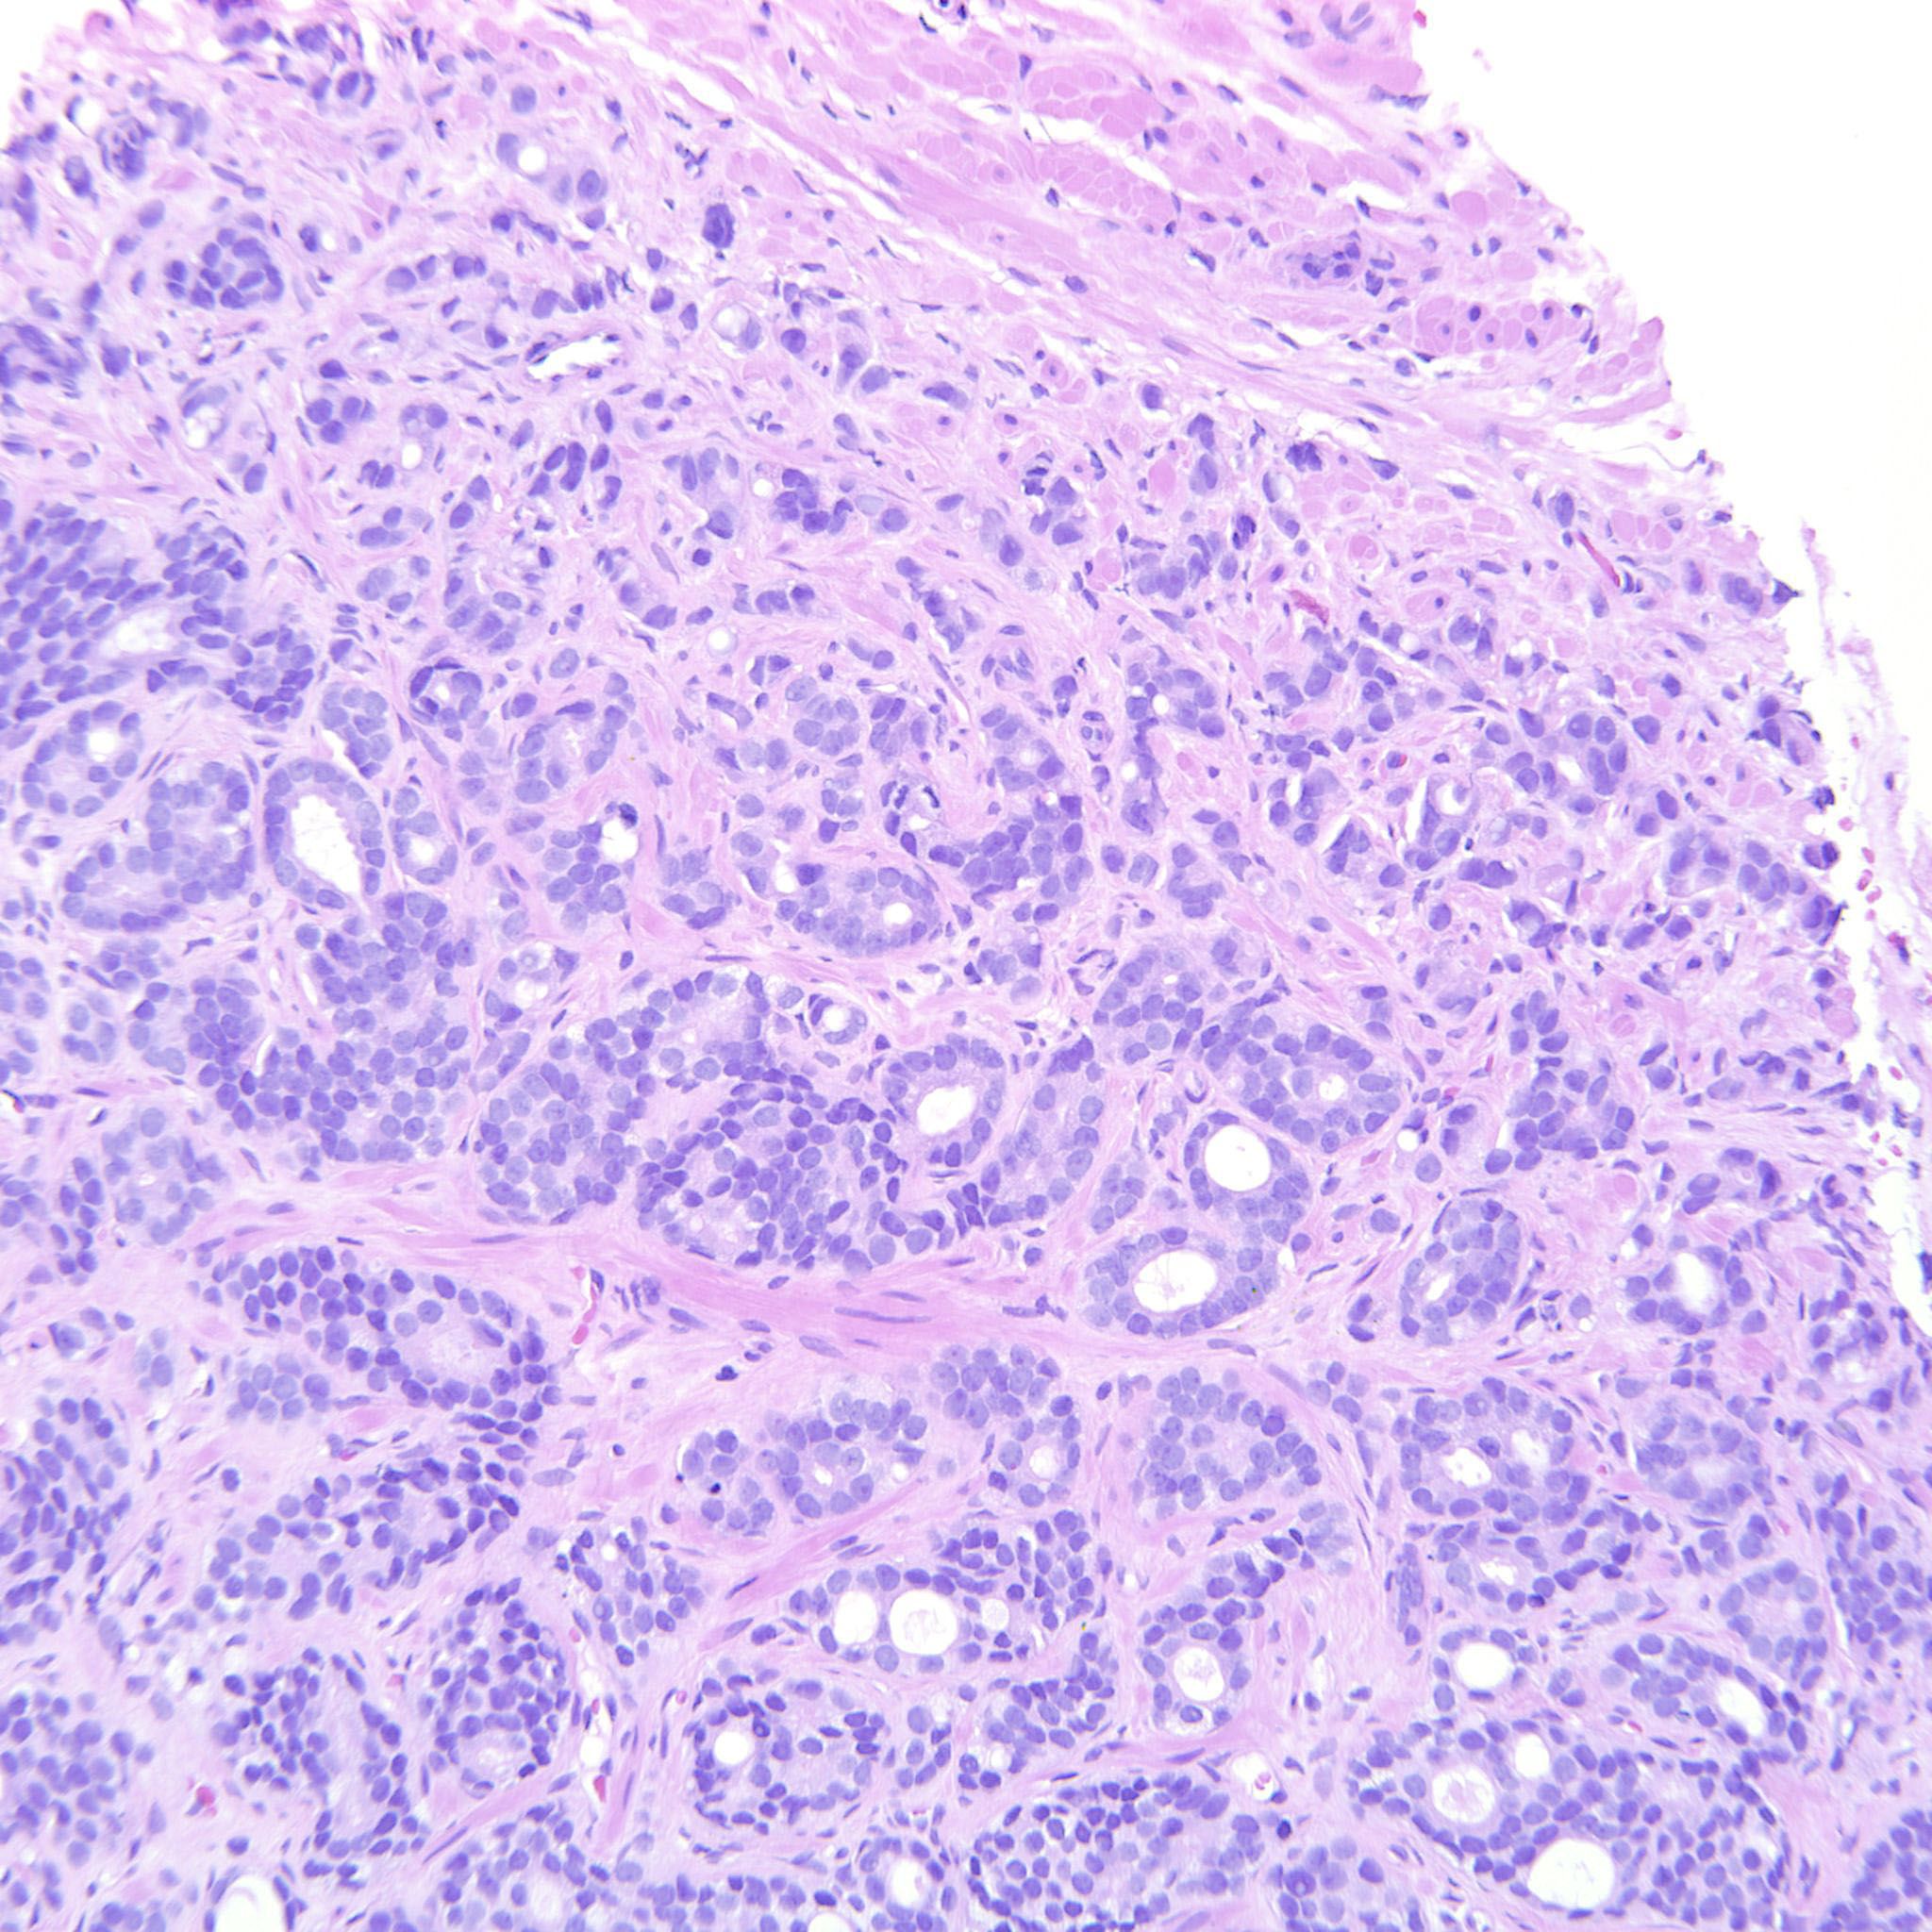

Consensus grade: GS 9-10 (ISUP 5)

Case description (by case creator):

The tumor is dominated by GP4 with mainly cribriform and fused glands but also some poorly formed glands. There is also a component of GP5 with single cells and indian files. These cells occupy an area that can be seen already at 10x. The GP5 component looks immature but is not suspicious for small cell carcinoma.